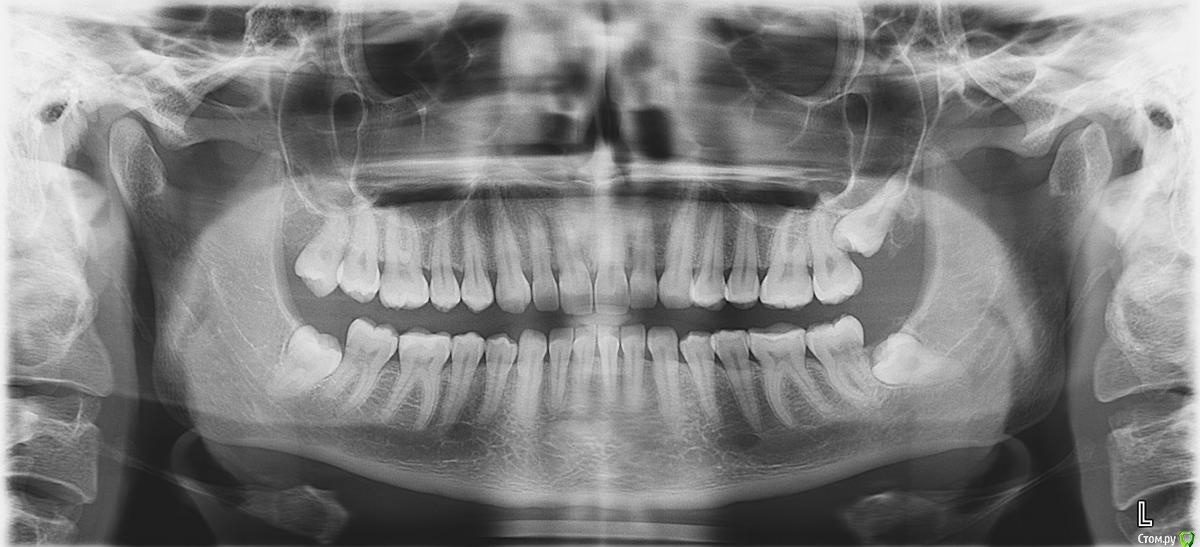

Коррекция дистального и глубокого прикуса

Я давно мечтала об идеальной улыбке и наконец-то решилась сходить к ортодонту.

У меня зубы более менее ровные, вот только с прикусом что-то не так.

После консультации ортодонта я была очень расстроена, так как мне было прописано удаление 8-ми зубов. 4-х мудрости (с этим я в принципе согласна и готова) и 4-х примоляров (они у меня совершенно здоровые) и брекеты на 1,5-2 года.

Для того чтобы подтвердить диагноз я решилась пойти еще к 3-мь специалистам и они мне озвучили тот же вердикт.

Только последний врач сказал что 4-ки удалять мне не нужно, так как моя нижняя челюсть и так слабо развита и в случае удаления примоляров у меня испортится профиль и будет прикус как у старушки. Ортодонт сказал, что нижнюю челюсть наоборот требуется выдвинуть вперед  с помощью брекетов и резинок. Только мне необходимо подрезать уздечку языка (якобы из за того что она плотнее чем нужно, она тянет нижнюю челюсть назад. Я слабо себе это представляю, но мне так озвучили).

Я не знаю кому верить, так как боюсь себе навредить и испортить лицо :( .

Возможно мне вообще требуется хирургическое вмешательство и любые брекеты только испортят ситуацию.

Мои снимки к письму прилагаются.